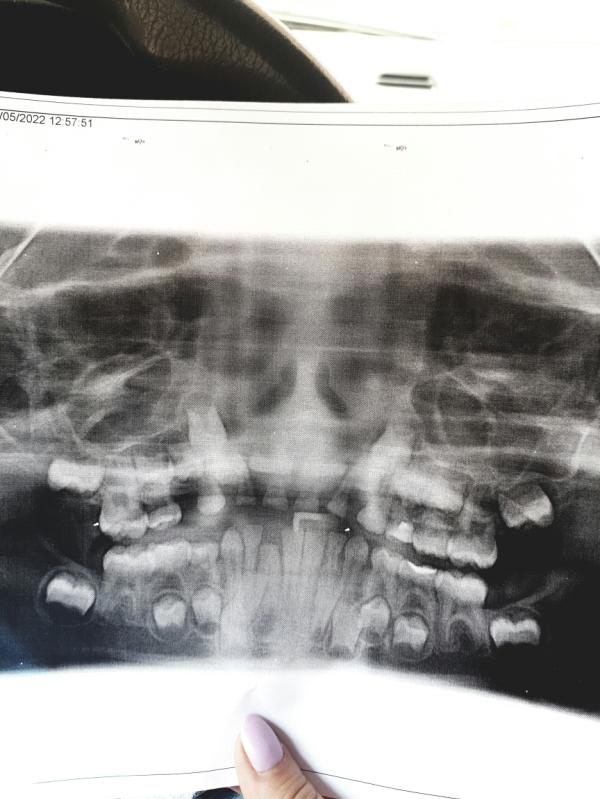

Мамочки, кто сталкивался с некомплектным зубом у ребенка 😨 ладно молочный лишний был, теперь и постоянный лезет, места в челюсти не хватает, получается молочный еще не выпал, а снизу сразу два лезет 😲😲😲 что делали в таких ситуациях

Ходили к ортодонту, удаляли сначала молочный, потом некомплектный. Потом брекеты около года носили. Сейчас ждем, когда у сына все зубы молочные поменяются и снова брекеты.

Обязательно обратитесь к хорошему ортодонту. Только она скажет как быть в вашем случае, и не затягивайте! Иначе вся челюсть кривая будет